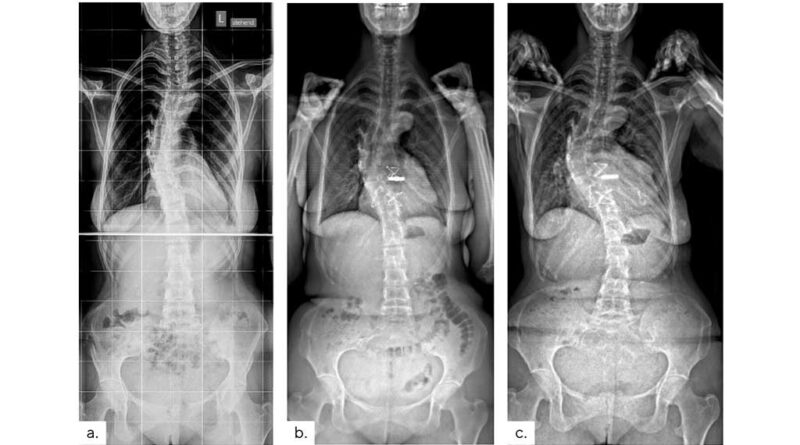

Sko­lio­se-Cobb-Win­kel – ein Ver­gleichs­wert mit Schwächen

A. Sel­le, J. Seifert

Der Cobb-Win­kel ist seit vie­len Jahr­zehn­ten der wich­tigs­te Ver­gleichs­wert zur Beur­tei­lung von Sko­lio­sen und zur Ein­tei­lung ent­spre­chen­der The­ra­pie­schrit­te. Er hat jedoch ent­schei­den­de Schwä­chen, die ins­be­son­de­re bei lang­bo­gi­gen und/oder stark rotier­ten Krüm­mun­gen zu gra­vie­ren­den Fehl­ein­schät­zun­gen und zur Ver­schlep­pung not­wen­di­ger The­ra­pien füh­ren kön­nen. Da sich das tat­säch­li­che Aus­maß einer sko­lio­ti­schen Defor­mi­tät im drei­di­men­sio­na­len Raum nur schwer quan­ti­fi­zie­ren lässt, wird der Cobb-Win­kel auf abseh­ba­re Zeit ein wich­ti­ger Refe­renz­wert blei­ben. Es ist umso bedeut­sa­mer, sei­ne Schwä­chen zu ken­nen und bei betref­fen­den Sze­na­ri­en ande­re Para­me­ter in die The­ra­pie-Ent­schei­dung einzubeziehen.